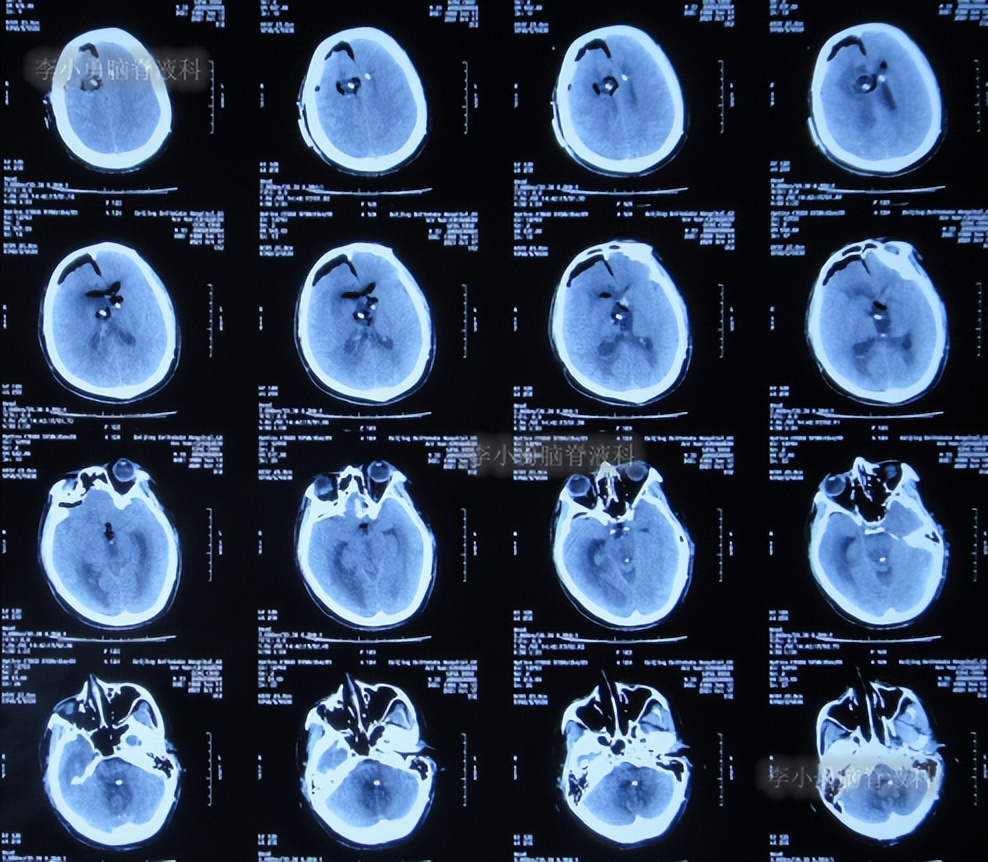

第2次的左侧脑室腹腔分流术后10天即2020年1月10日,查头颅CT示脑室仍有扩张(图-7)。

图-7:2020年1月10日头颅CT

第2次的左侧脑室腹腔分流术后18天即2020年1月18日,查头颅CT示脑室有缩小(图-8)。

图-8:2020年1月18日头颅CT